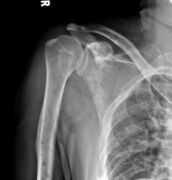

The diagnostic examination of a person with suspected multiple myeloma typically includes a skeletal survey. This is a series of X-rays of the skull, axial skeleton, and proximal long bones. Myeloma activity sometimes appears as "lytic lesions" (with local disappearance of normal bone due to resorption) or as "punched-out lesions" on the skull X-ray ("raindrop skull"). Lesions may also be sclerotic, which is seen as radiodense.[70] Overall, the radiodensity of myeloma is between −30 and 120 Hounsfield units (HU).[71] Magnetic resonance imaging is more sensitive than simple X-rays in the detection of lytic lesions, and may supersede a skeletal survey, especially when vertebral disease is suspected. Occasionally, a CT scan is performed to measure the size of soft-tissue plasmacytomas. Nuclear Medicine Bone scans are typically not of any additional value in the workup of people with myeloma (no new bone formation; lytic lesions not well visualized on nuclear bone scan).

Multiple myeloma in the upper arm